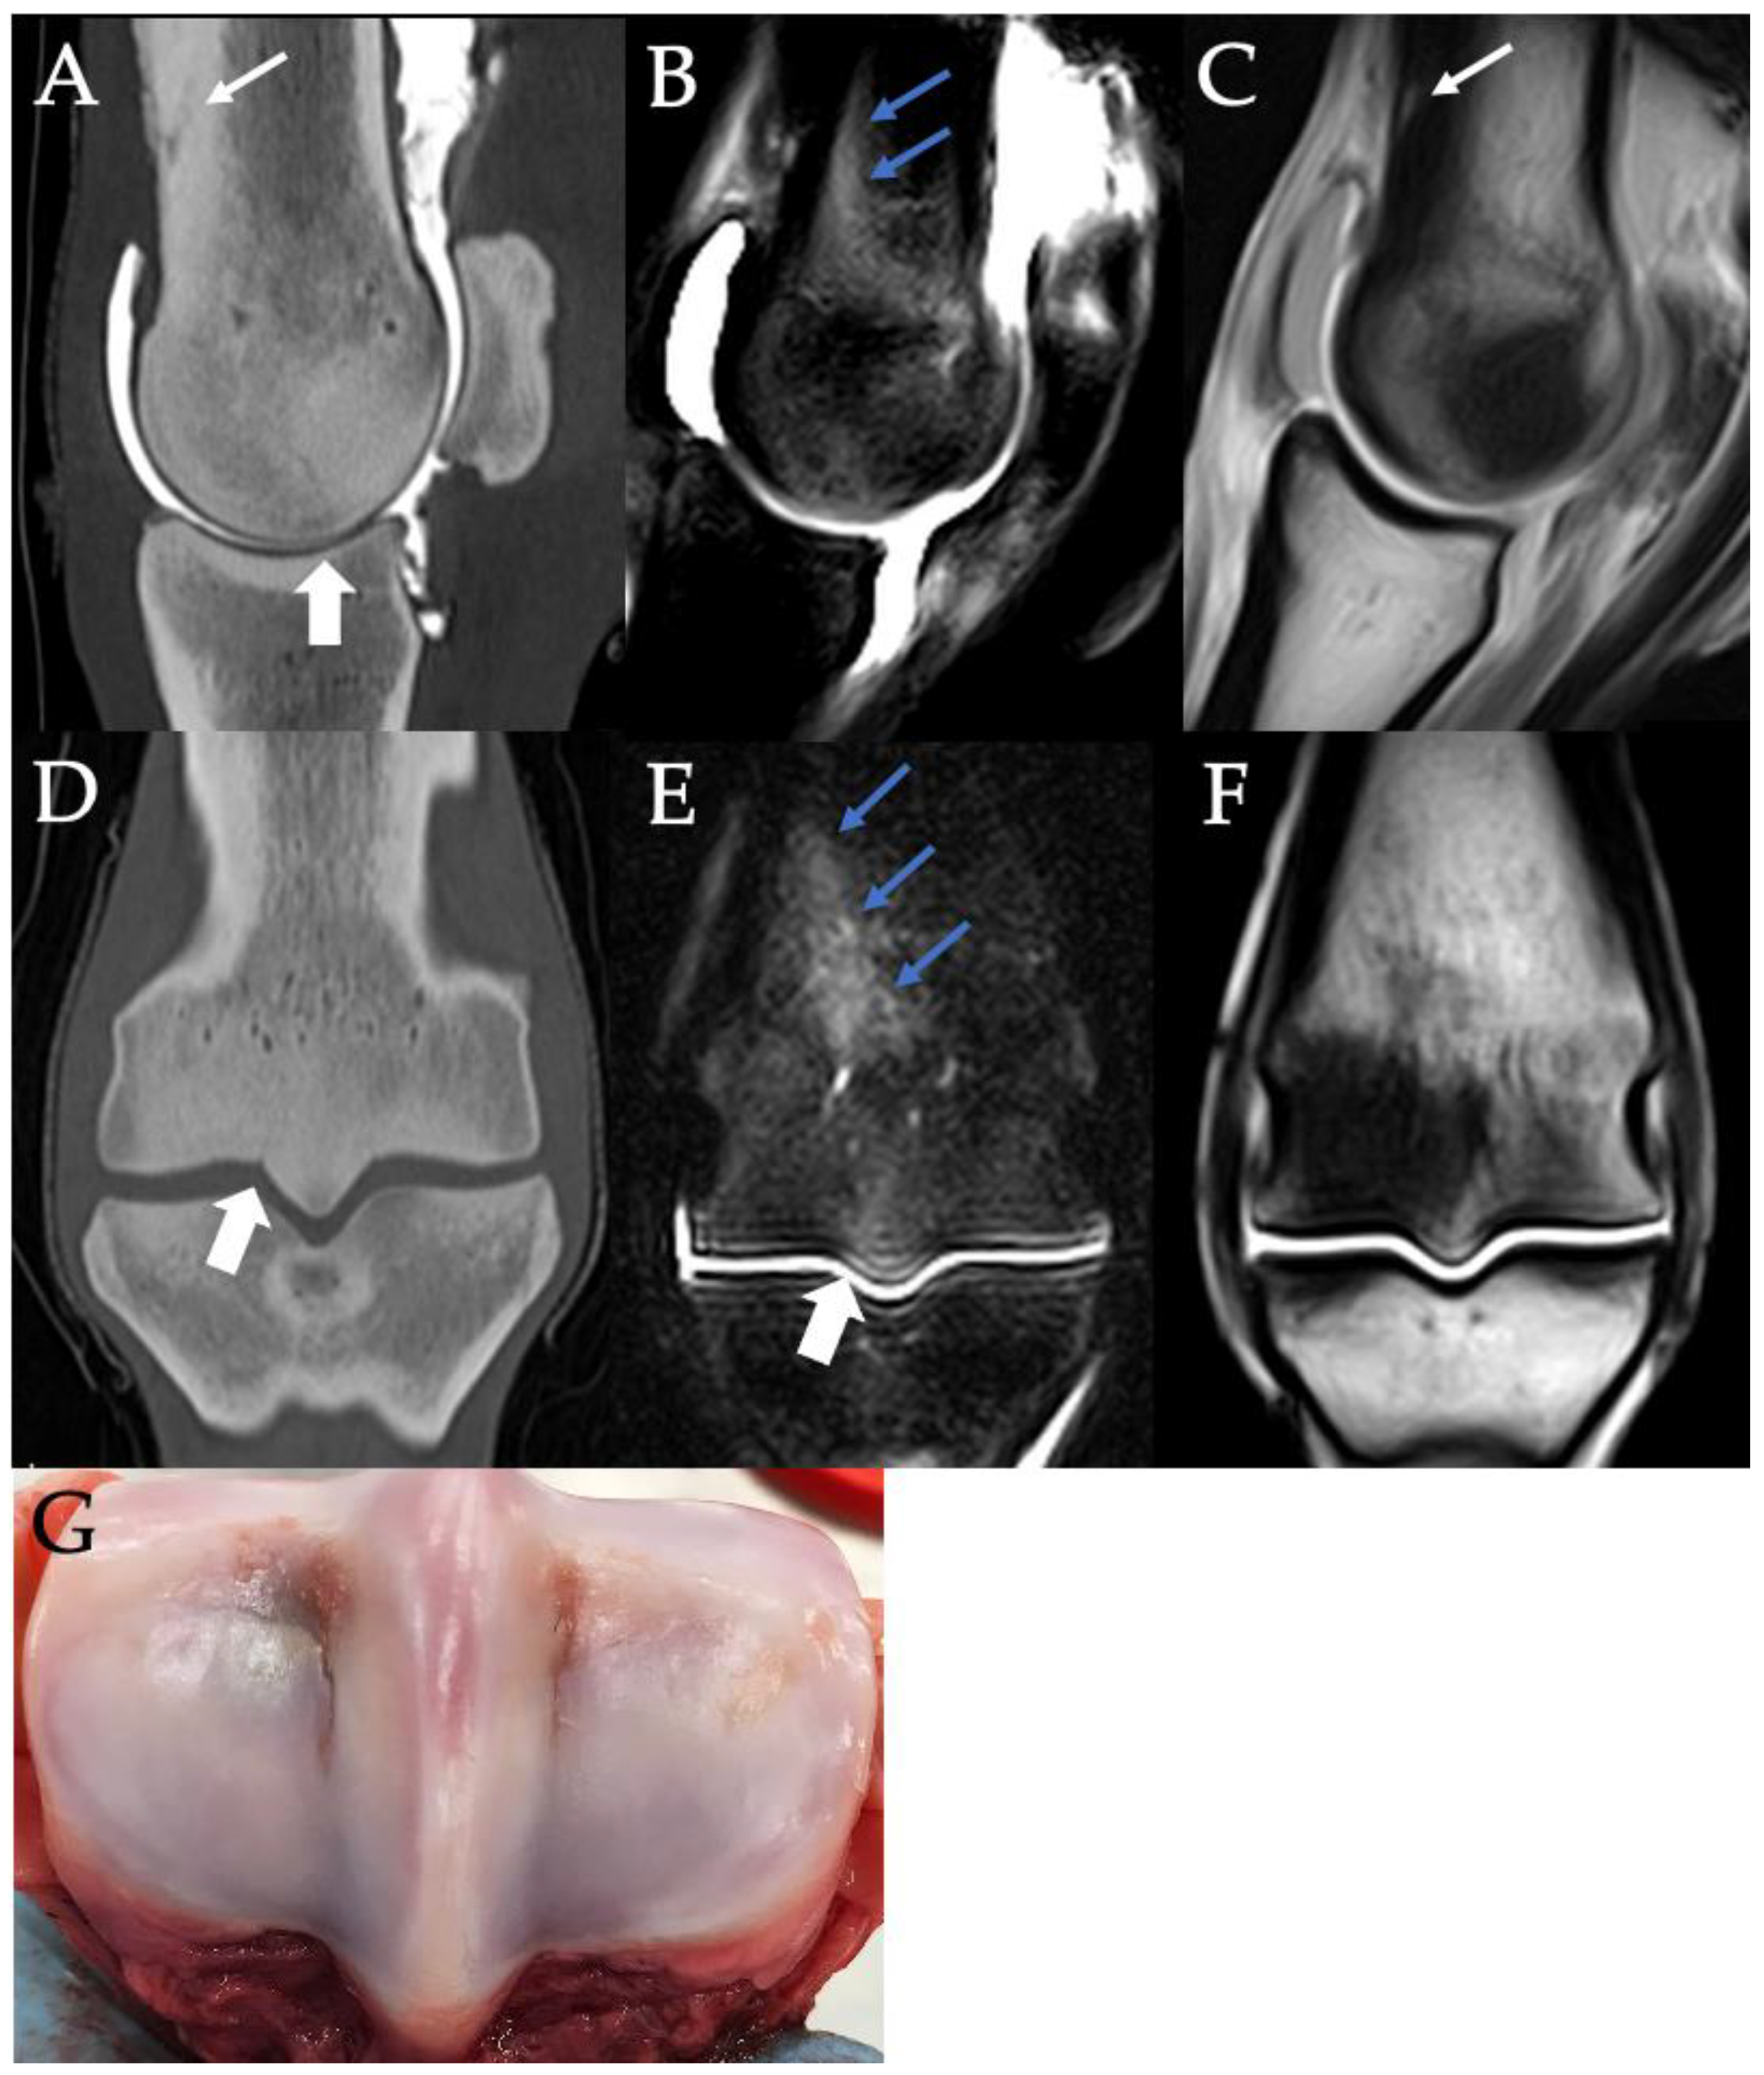

3.3. PSG Subchondral Bone Lysis

3.4. PSG Subchondral Bone Defects

3.5. PSG Cartilage Defects

3.9. Histopathology